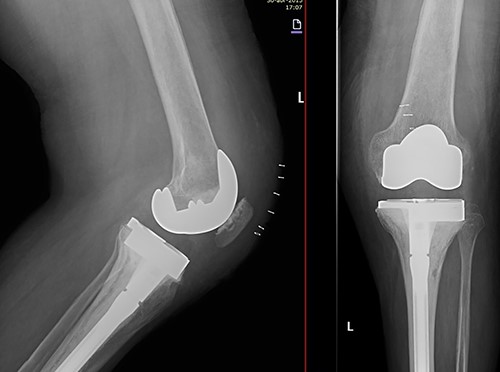

Due to the poor bone quality and defect associated to osteonecrosis (Fig. 3), osteosynthesis was discarded and total knee arthroplasty (TKA) was performed with lateral tibial block and diaphyseal stem (Fig. 4). Microbiological samples confirmed the absence of infection. Pathological samples confirmed osteolysis and chronic synovitis with osteoporosis and osteonecrosis, leading to the pathological fracture (Figs 5 and 6).

X-ray of the left knee showing reconstruction with 10-mm tibial lateral block and a tibial diaphyseal stem.